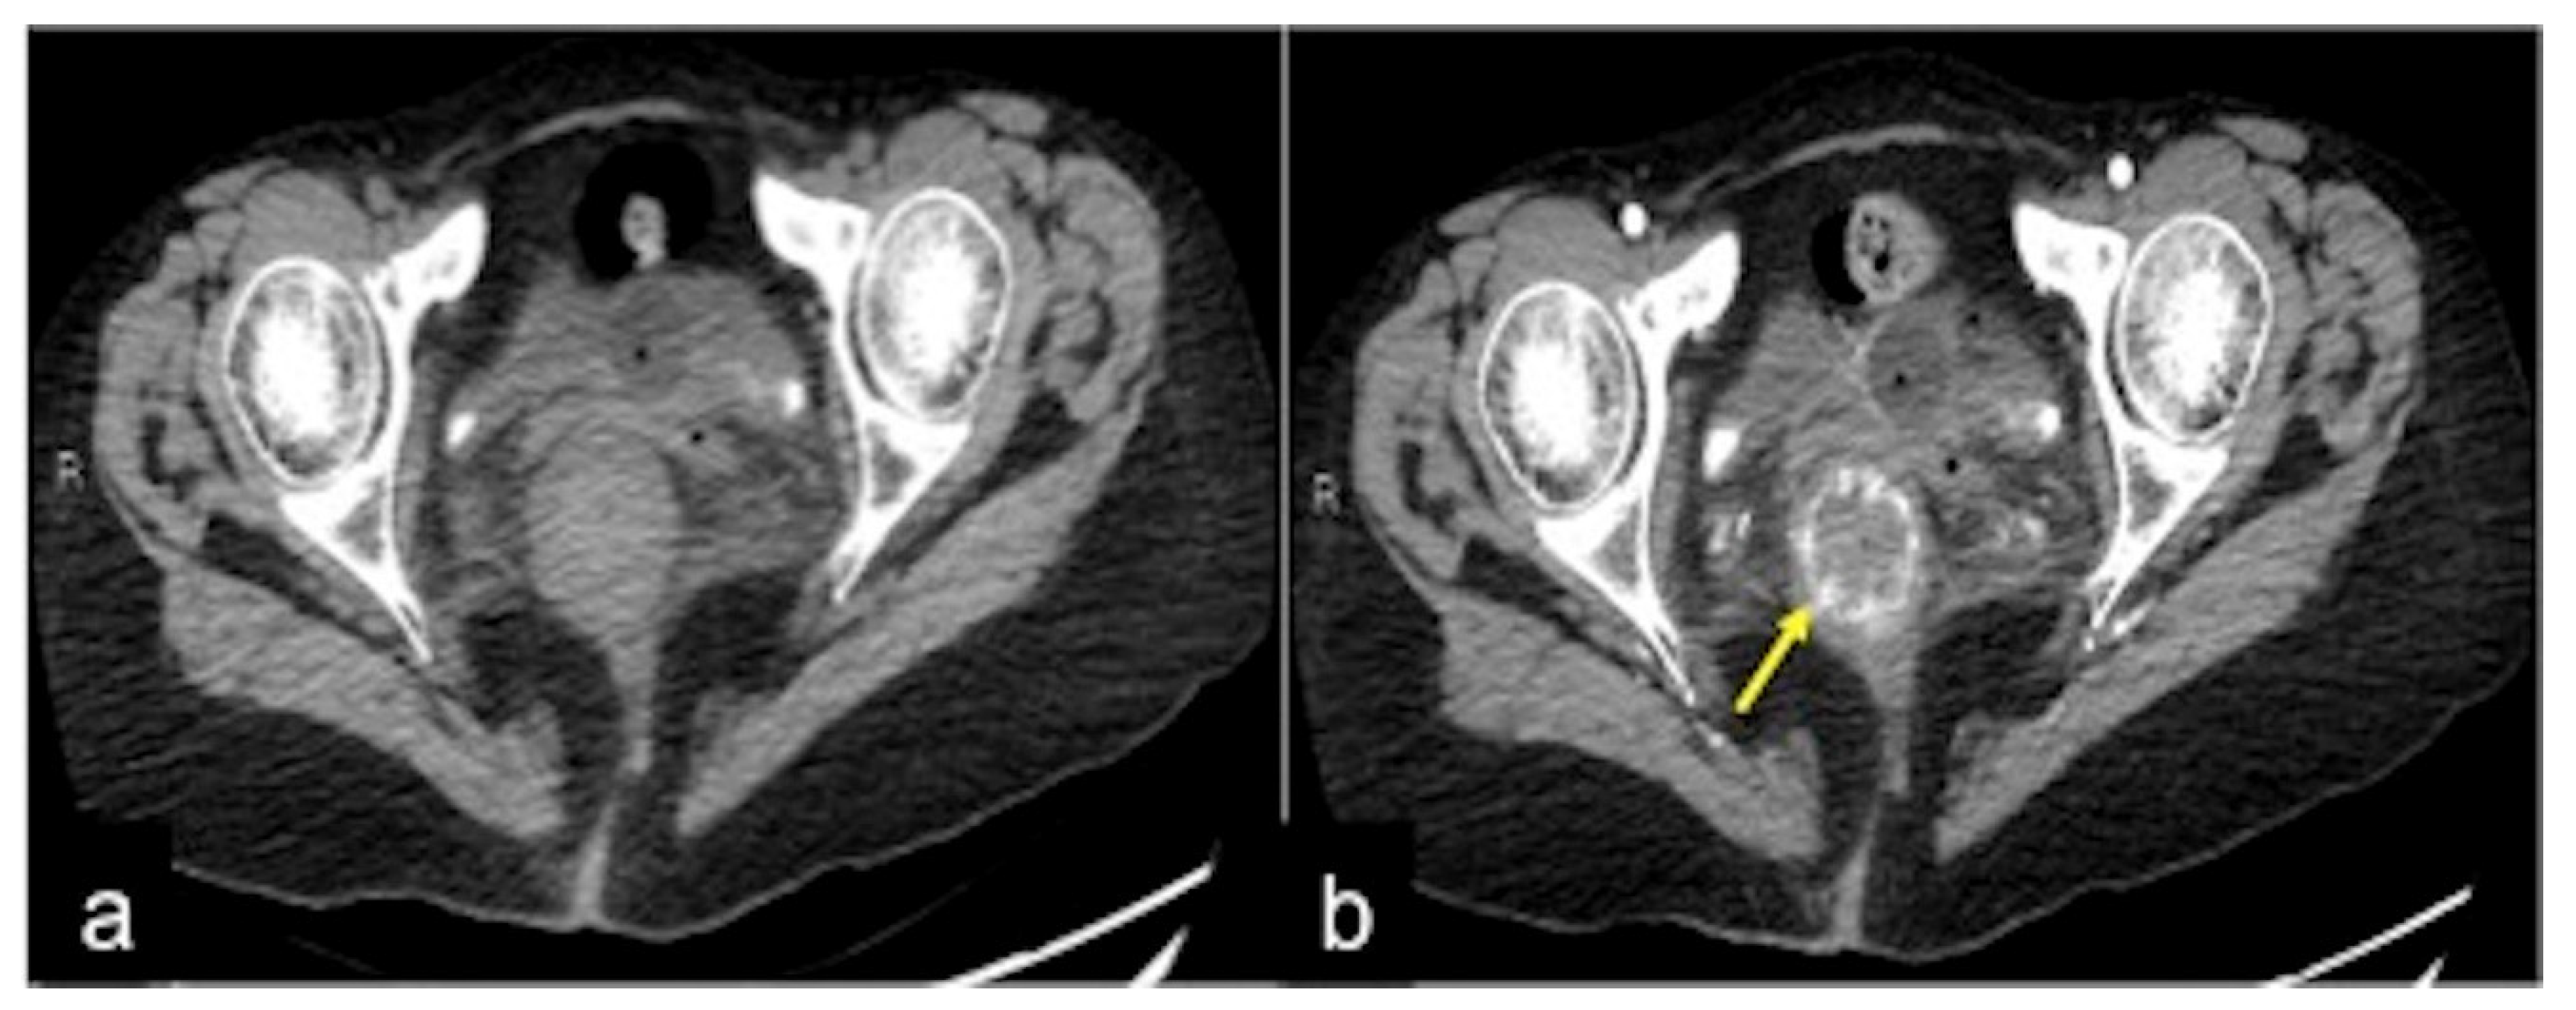

| Rectal Varices and Haemorrhoids (Figure 35) | Pain and/or bleeding. | Dilated veins with possible bleeding visible in the portal phase; rectal varices are located proximal to the linea dentata while haemorrhoids are located in the anus. |